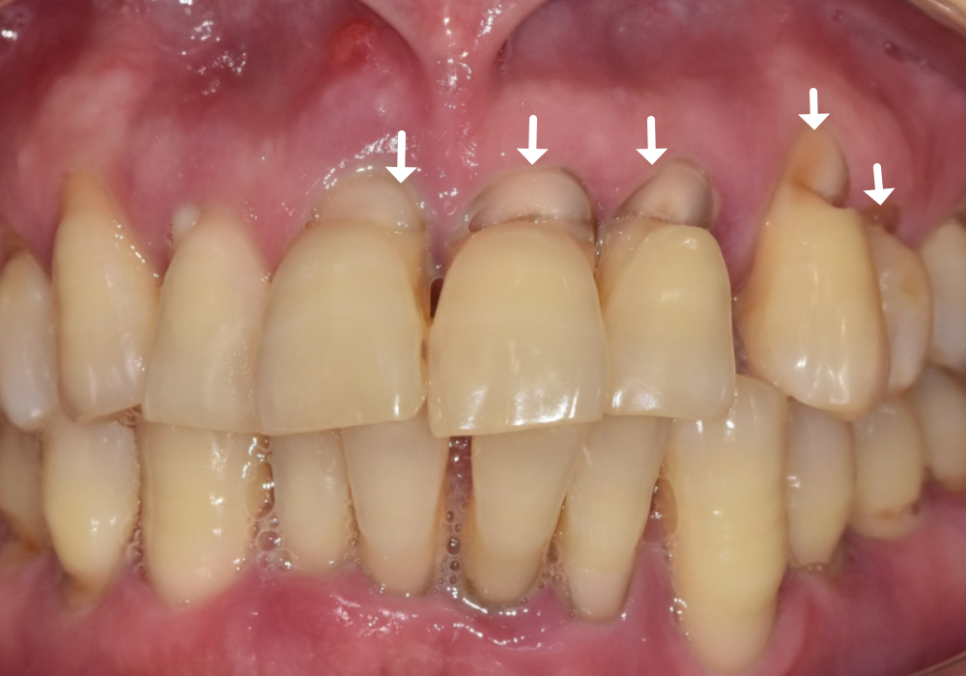

환자분께서는 앞니 부위라

심미적인 부분도 중요하게 생각하셨기에

치아색에 맞는 레진으로

꼼꼼하게 메워드리는 치료를 진행했습니다.

250417

잇몸 라인과 치아 색상을 자연스럽게 맞춰드려

심미적으로 아주 만족스러운 결과가 나왔네요.^^

241224 (전) 250417(후)